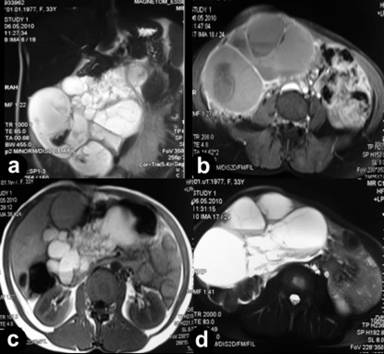

A 33-year-old woman, presented with a short history of abdominal enlargement, early satiety, epigastric fullness and a slight weight loss. Physical examination revealed a huge mass occupying almost the whole abdominal cavity on inspection and palpation. All routine blood tests including tumor markers were within normal limits, except a slight anemia. An abdominopelvic MRI showed a multiloculated, lobulated T1 hypo/hyper, T2 hyperintense cystic mass extending from right subhepatic space to the pelvis measuring 155x167x100 mm with contrast fixation at its wall and septae (Figure 1). Both ovaries were distinctly normal. As the mass was symptomatic, though its nature and origin was obscure, a laparotomy with diagnostic but also therapeutic intent was planned. The exploration revealed a huge mass inseparable from the transverse mesocolon and the greater curvature of the stomach, eventually originating from the head-body junction of the pancreas (Figure 2). A pancreaticoduodenectomy was performed encompassing also the concerned distal stomach and transverse colon. The postoperative recovery was uneventful. Histopathology revealed a partly cystic, partly cavernous lymphangioma originating from the pancreas. The neighboring structures (transverse colon and distal stomach) were intact as well as twelve dissected lymph nodes. The covering epithelium of lymphatics was positive for D240 immunostain. (Figure 3). The patient is disease and symptom-free at her 18th month check-up.

Figure 1. a. Coronal T2-weighted image shows the multiloculated cystic mass extending from right sub-hepatic space to the pelvis. b. Axial T1-weighted image depicts the thin walls and multiple fine septations enhanced after intravenous contrast injection and fluid levels with different intensity. c. Axial T1-weighted image shows the multiloculated, multiseptated hyperintense lesion in the pancreatic space. d. A more caudal axial T2-weighted image showing multiloculated hyperintense cystic mass with fluid levels and multiple septations. |